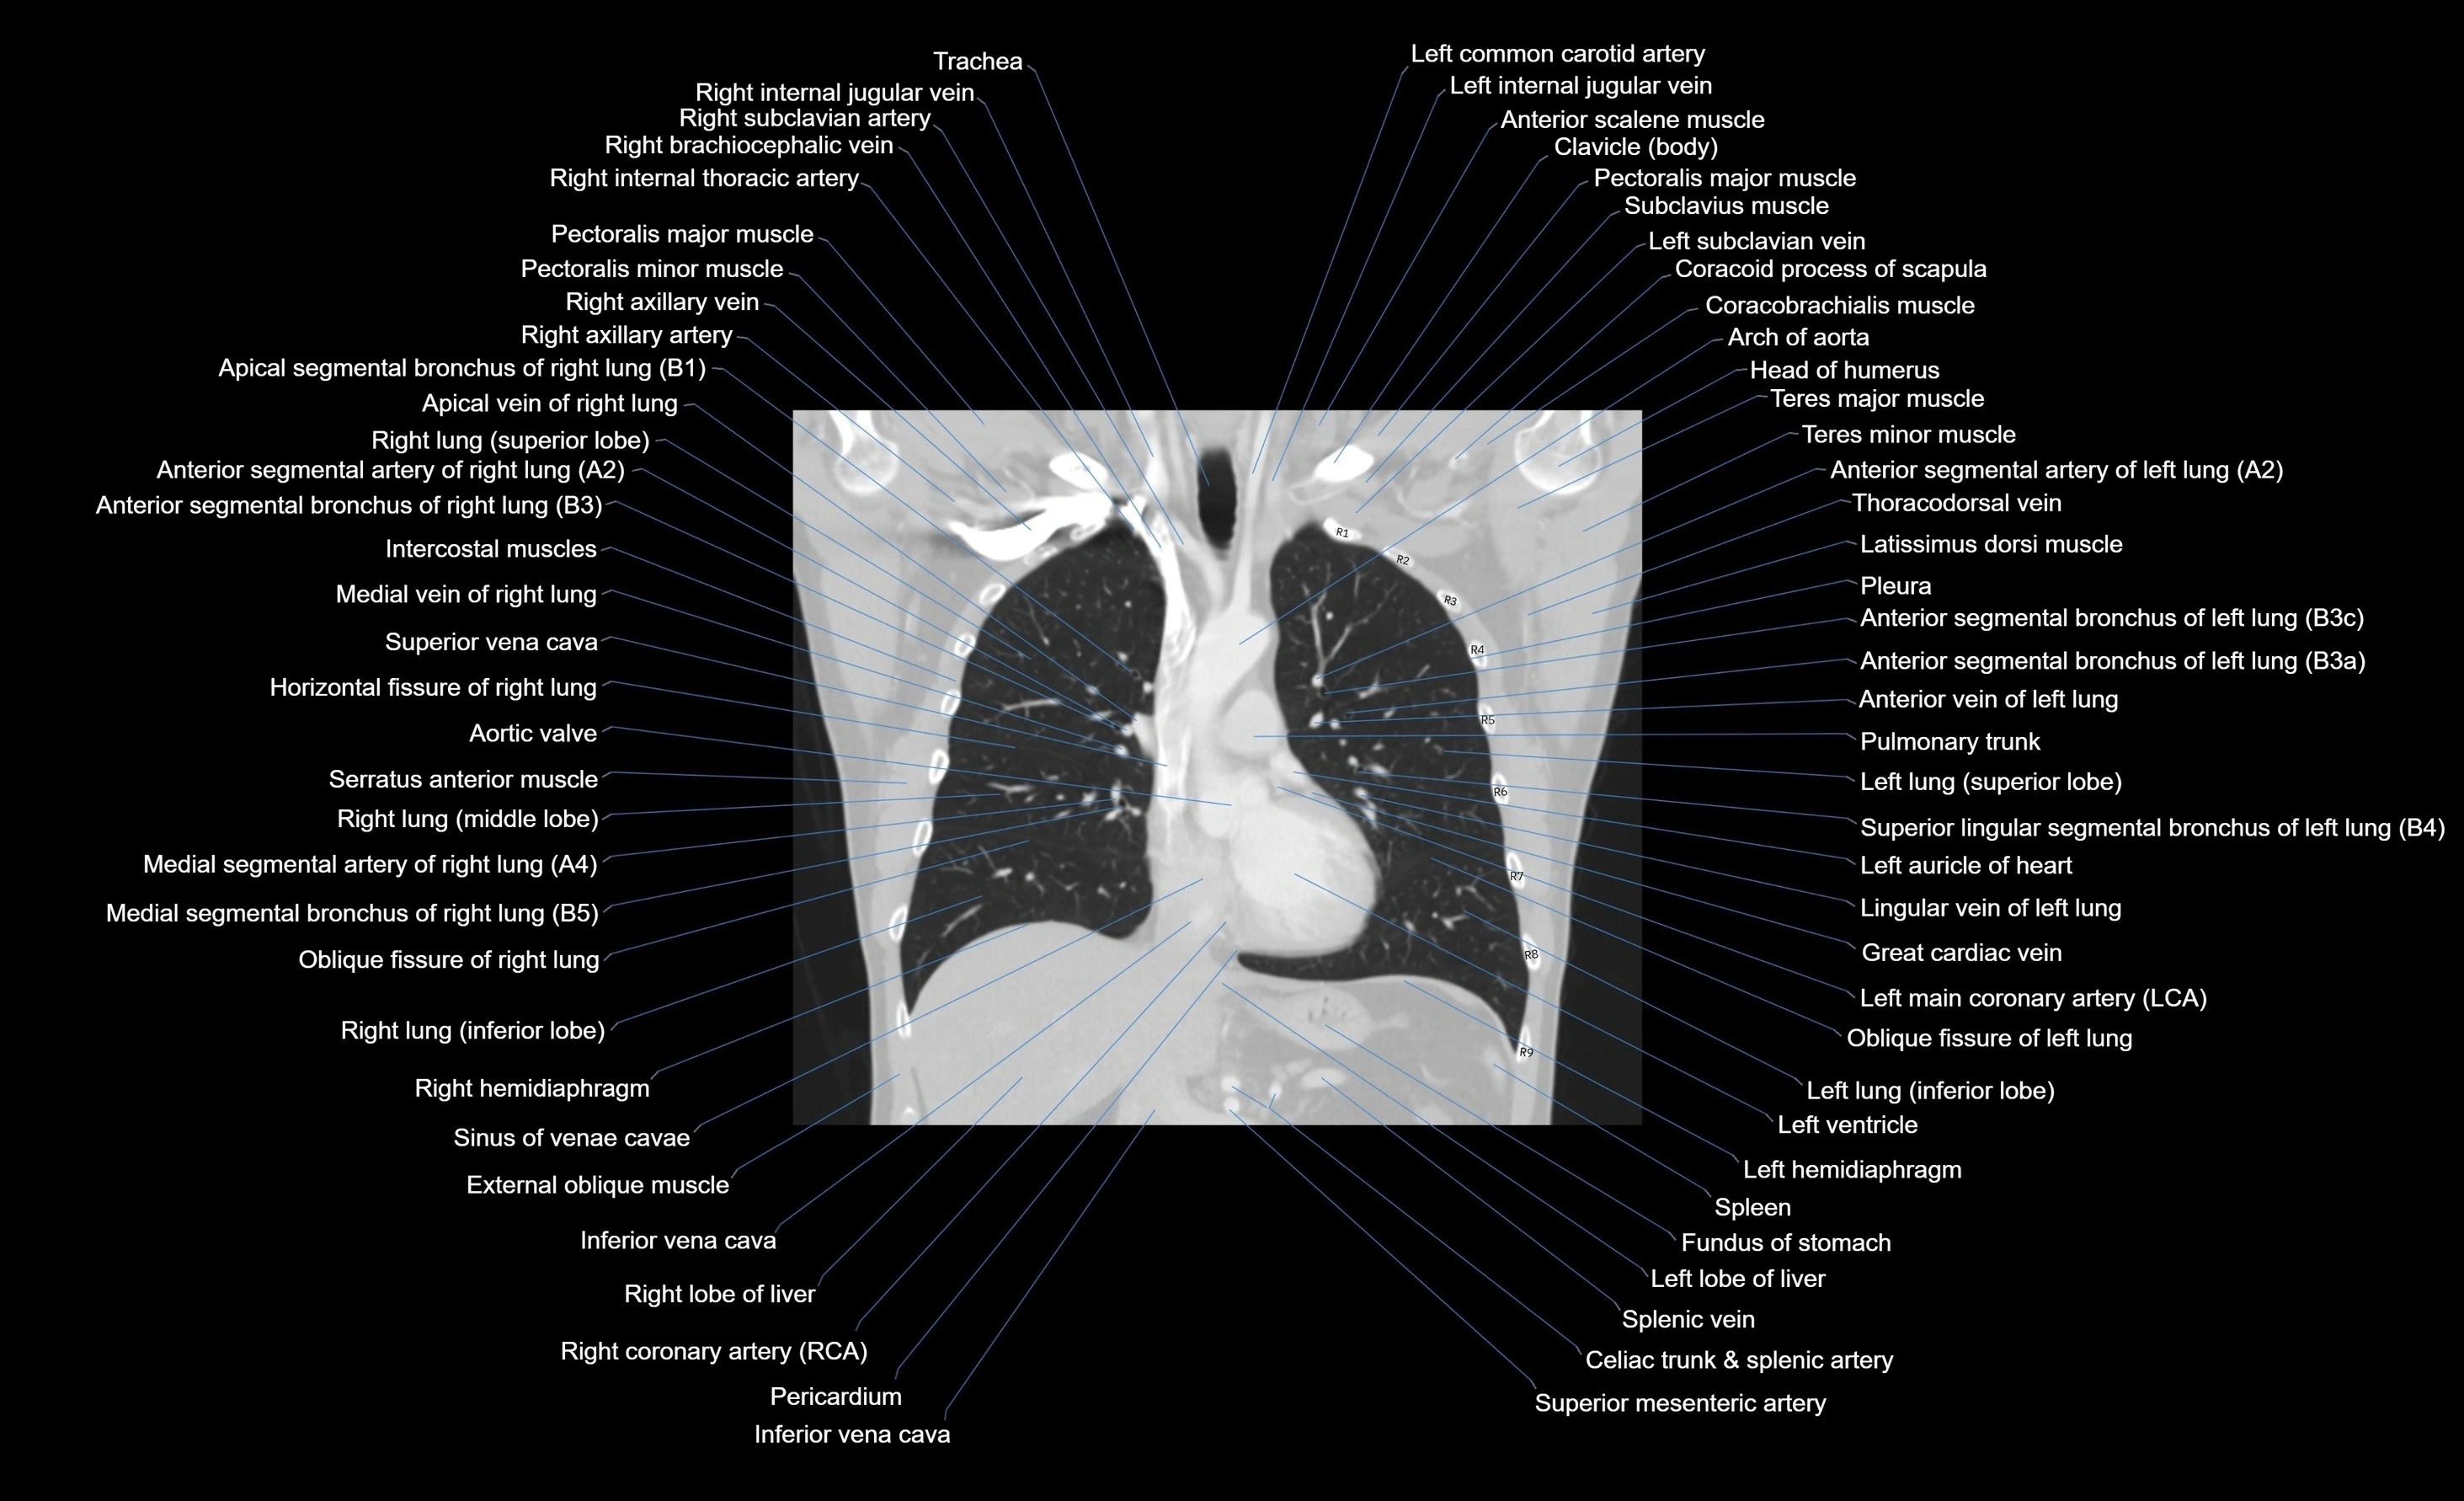

CT images